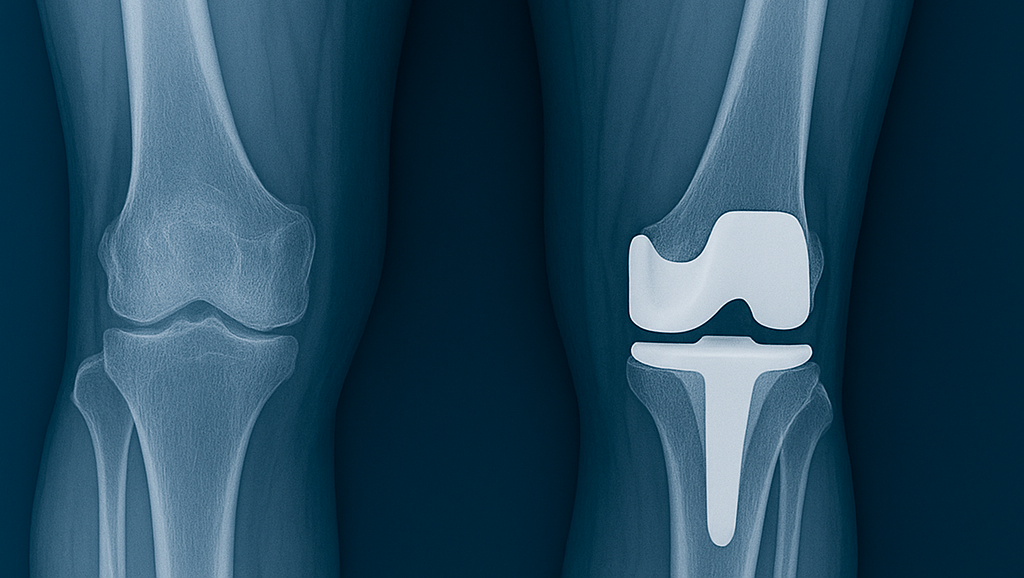

Diz, kalça ve omuz kireçlenmelerinde protez cerrahisi, ağrısız yaşam ve hareket özgürlüğü imkanı sunar.

Diz ve Kalça Protezi

Kireçlenme (artroz) tedavisinde başarılı protez cerrahisi için iyi bir planlama şarttır. Bunun için çok sayıda ameliyat deneyimi ile birlikte kullanılan protez malzemelerinin kalitesi büyük önem taşır. Diz ve kalça protezlerinin tarihçesini bilmek, farklı tekniklere hâkim olmak ve tüm cerrahileri uygulamış olmak, ameliyatın başarısını ve hastanın yaşam kalitesini doğrudan etkiler.